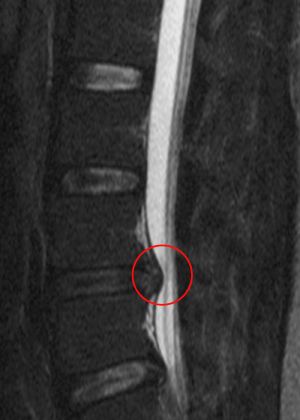

표시된 부분이 압박된 신경근]]3. 2. 감별 진단

'''빨간 원 안은 '압박된 신경근' 및 '수분 함량이 부족하고 염증을 일으켜 위로 크게 돌출된 추간판'''']]

'''위 이미지의 고농도 버전'''